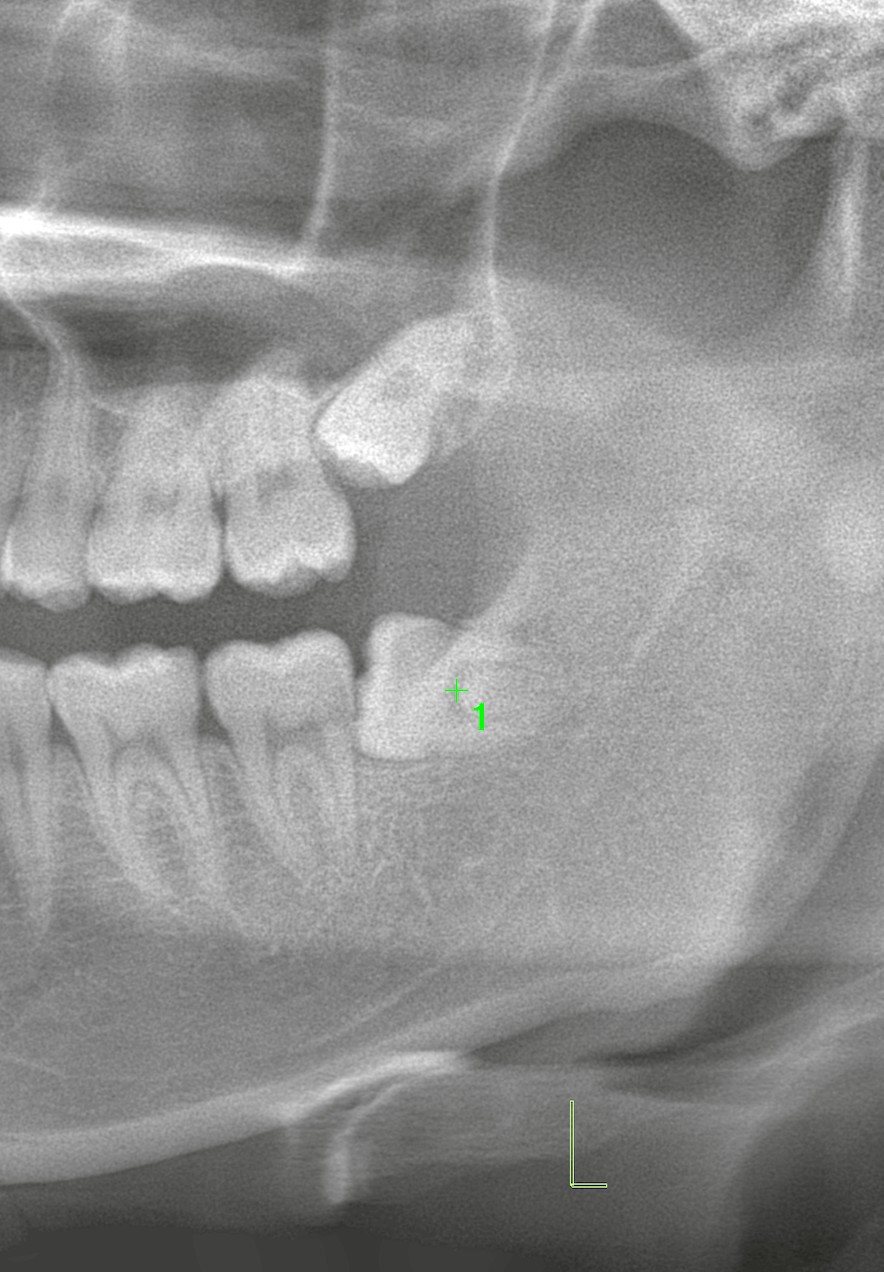

本日は「左側の上下の親知らずを同時に抜歯したケース」についてご紹介します。

下顎の親知らず

左下の親知らずは、水平に埋まっているタイプで、定期的に腫れを繰り返す状態でした。

水平埋伏智歯は歯ブラシが届きにくく、清掃不良から腫脹や炎症を起こしやすいのが特徴です。

他院では「神経に近いため抜歯せず経過観察」と言われていましたが、当院でCT撮影を行った結果、下歯槽神経との距離は十分にあることが確認できました。そのため、安全に抜歯可能と判断しました。

上顎の親知らず

左上の親知らずは痛みはありませんでしたが、患者様ご本人の希望もあり同時に抜歯を行うことになりました。

上顎の場合、上顎洞との位置関係がリスクとなります。埋伏しているため、一部切開を加え、必要に応じて分割しながらの抜歯が必要です。事前に「上顎洞穿孔のリスク」についてしっかりご説明しました。